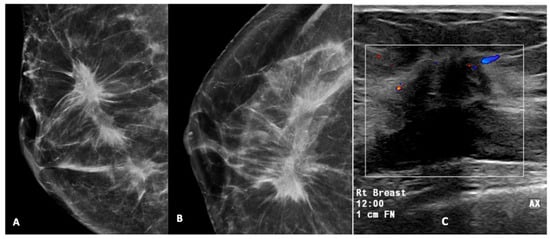

Figure 2, Figure 3, Figure 4, Figure 5 and Figure 6 show examples of the different microcalcification morphologies and distributions, while Figure 6 shows an example of a mammographic mass and an image of a complementary ultrasound assessment of the mass.

Figure 6.

High-density mass with spiculated margin in the upper outer quadrant, associated with pleomorphic calcifications (A,B). A USG of this lesion (C) showed a hypoechoic mass with a spiculated margin, posterior acoustic shadowing, and internal vascularity on Doppler. This was reported as a BI-RADS 5 lesion. USG-guided biopsy was performed and was found to be HPE-proven invasive carcinoma. (Rt breast—right breast, 12.00—12 o’clock position, 1 cm FN—1 cm from nipple). The box represent the lesion and colour area represent blood flow.